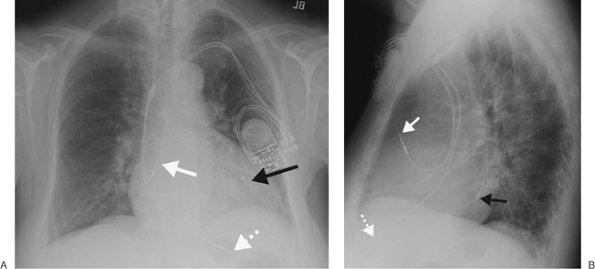

FIGURE 5-11. Pulmonary artery pseudoaneurysm as a complication of pulmonary artery catheter placement. A: AP recumbent chest radiograph in a 66-year-old woman with a history of chronic obstructive pulmonary disease and prior lung volume reduction surgery. The film was taken shortly after right heart catheterization, during which time a pulmonary artery catheter was placed into the right pulmonary artery to measure pulmonary capillary wedge pressure. The radiograph shows diffuse airspace disease in the right lung, consistent with acute pulmonary hemorrhage, which was new compared with a precatheterization radiograph. B: CT scan obtained after administration of intravenous contrast material, performed the same day as the chest radiograph in (A), shows an enhancing peripheral pulmonary artery pseudoaneurysm (arrows), with surrounding pulmonary hemorrhage (arrowheads). The pseudoaneurysm was embolized with coils by interventional radiologists, and the bleeding stopped.